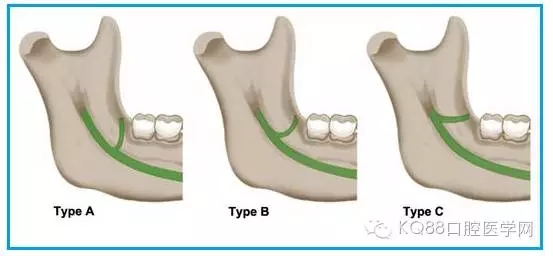

圖一 磨牙后區(qū)的形態(tài)學分類(綠色標示):

A.水滴形;

B.細長型;

C.三角形。

圖三 磨牙后管三種走行方向示意圖:

Type A.垂直走行;

Type B.斜向走行;

Type C.水平走行。